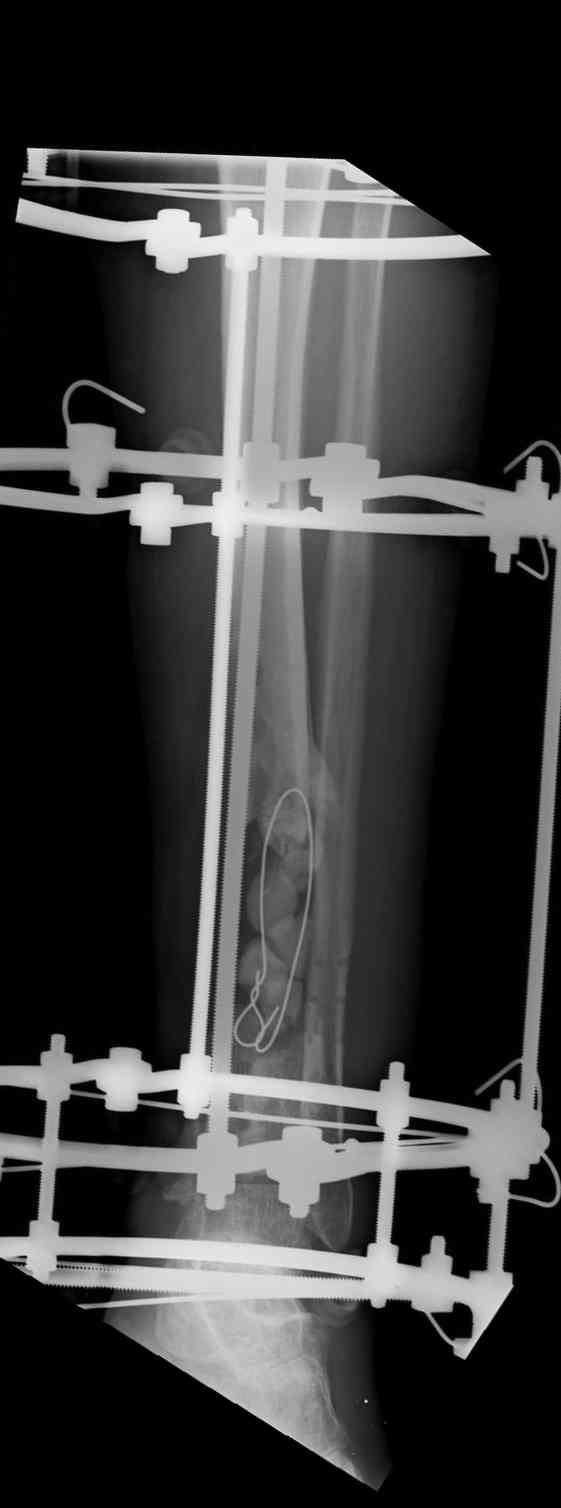

Re: Дефект и остеомиелит tibia